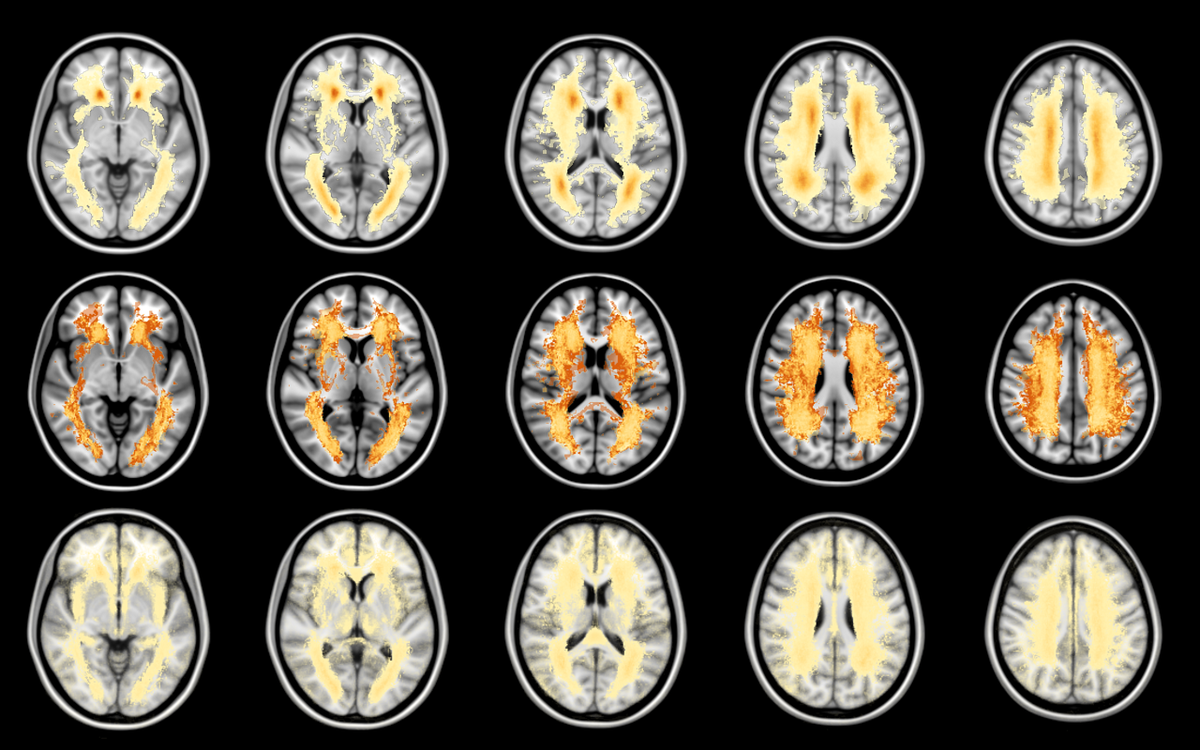

Beeldherkenningssysteem klinisch toegepast

Onderzoeker Hugo Kuijf schreef een wedstrijd uit: wie heeft het beste computerprogramma om hersenscans te beoordelen op dementie en Alzheimer? De winnaar deed het beter dan de radioloog ooit zal kunnen met het blote oog.

Als je veel scanbeelden samenbrengt in een zelflerend computerprogramma, kan de software bij nieuwe patiënten zelf een diagnose stellen. Algoritmes – oftewel rekenprogramma’s – analyseren de beelden razendsnel. “Machine learning is hot”, zegt onderzoeker

, die in Utrecht dit soort programma’s maakt voor de diagnose dementie en Alzheimer. “En iedereen beweert dat hún systeem beter is dan dat van alle andere. Er komen elke dag nieuwe zelflerende systemen bij, die volgens de makers nóg beter zijn.”

Hugo wilde weten welke systemen het meest betrouwbaar zijn, ongeacht het type scanner dat is gebruikt om de scanbeelden te maken en ongeacht afleidende details en nuances op de beelden. Hij schreef een internationale wedstrijd uit onder zijn collega’s. Hij stuurde ze een aantal scans op van mensen met dementie en alzheimer, gemaakt op vijf verschillende type scanners. Hij vroeg hen die te beoordelen met hun eigen beeldherkenningssysteem.

Hugo vergeleek de resultaten met scanbeelden die hij had achtergehouden. Zo kon hij beoordelen of de dertig ‘machines’ met hun algoritmes goede diagnoses hadden gesteld. “Sommige zelflerende systemen deden het opmerkelijk goed”, zegt hij. “Maar er waren ook systemen die er weinig van bakten.” De uiteindelijke winnaar was een team van de vooraanstaande Sun Yat-sen universiteit uit China.

Beter dan de radioloog

Onder de groep winnaars zijn zelfs zelflerende systemen die scanbeelden beter beoordelen dan de radioloog zelf. Hugo: “Een radioloog beoordeelt beelden met het blote oog. Maar de computer geeft cijfers over maat en getal.” Uiteraard blijft de radioloog altijd

. Hugo Kuijf: “Machine learning is nu nog een hulpmiddel. Het zal de radioloog voorlopig zeker niet vervangen.”